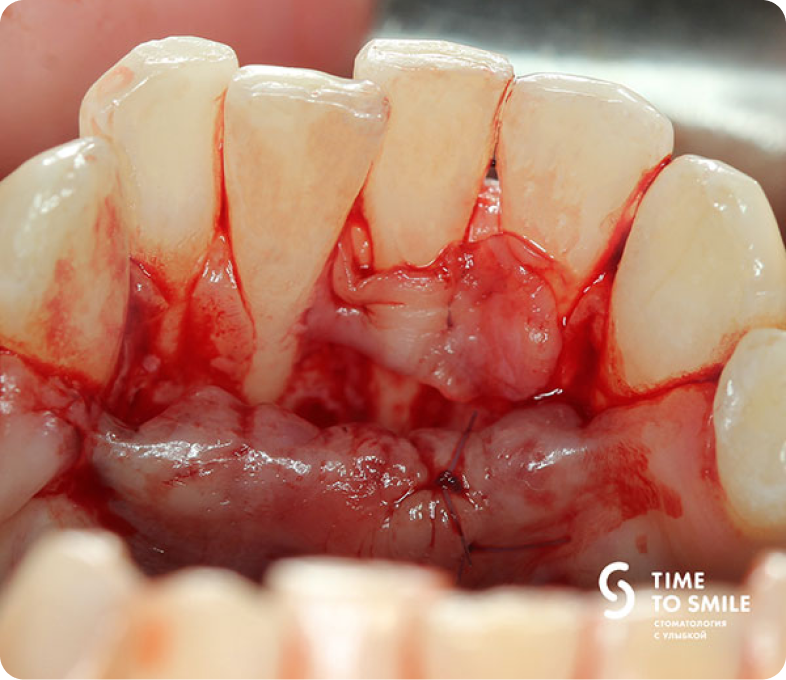

В ходе лечения проведена операция по закрытию дефекта с использованием десневого трансплантата из области твердого нёба.